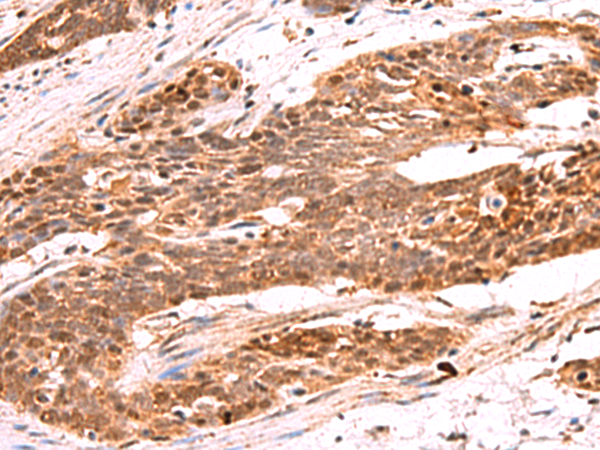

IHC (Immunohiostchemistry)

(Immunohistochemistry of paraffin-embedded Human esophagus cancer tissue using RRP8 Polyclonal Antibody at dilution of 1:80(×200))